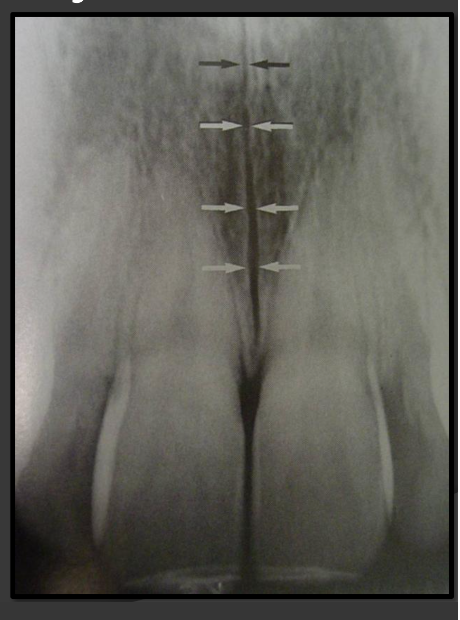

How does the median palatine suture present in a radiograph?

A thin radiolucent line that runs directly between the maxillary incisors.